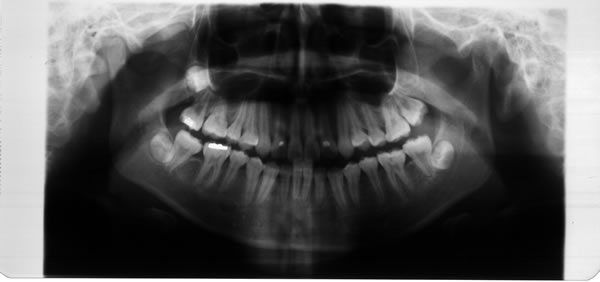

2、固定矫治器 它粘固在牙齿上,可以精确地移动牙齿,能够矫治各种复杂的错合畸形,矫治效果好,是目前国内外最常使用的矫治器。各种固定矫治器大都由带环、矫治弓丝、托槽等三部分组成。我国自从开展固定正畸以来,先后用过Begg细丝弓矫治器、方丝弓矫治器、直丝弓矫治器来矫治错合畸形。目前国内普遍采用的是直丝弓矫治器。按照直丝弓托槽的槽沟角度的不同设计,常用的直丝弓矫治器又可分为Roth系列直丝弓矫治器、OPA-K直丝弓矫治器、MBT直丝弓矫治器等。按照托槽所用材质的不同,可以分为国产金属托槽、进口金属托槽、生物陶瓷托槽。